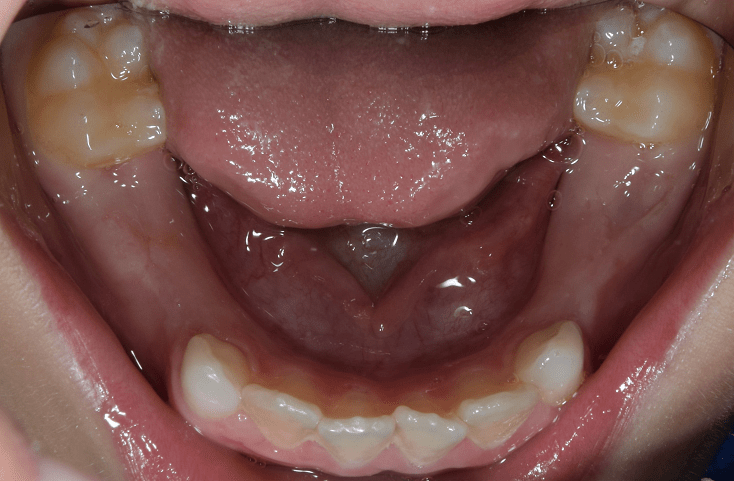

A csavarokon kívül rugók is építhetők az aktív kivehető készülékekbe. Ezek a rugók/karok általában az elülső fogak közötti rések összezárására használatosak (záró rugók). Ilyen célra én nagyon ritkán alkalmazom őket, mivel az aktív lemezekkel végzett részárás ritkán ad megfelelő végeredményt. Ilyenkor gyakorlatilag csak a fogak koronai részének egymás felé döntése történik. A rugók, karok kiválóan használhatók az oldalsó fogak területén a különböző rések megtartására, visszanyerésére (nyitó rugók). Például egy korai tejfogeltávolítást (lsd. a képen) követően ilyen karok segítségével a foghiány mérete megőrizhető, a szomszédos fogak vándorlása megelőzhető.